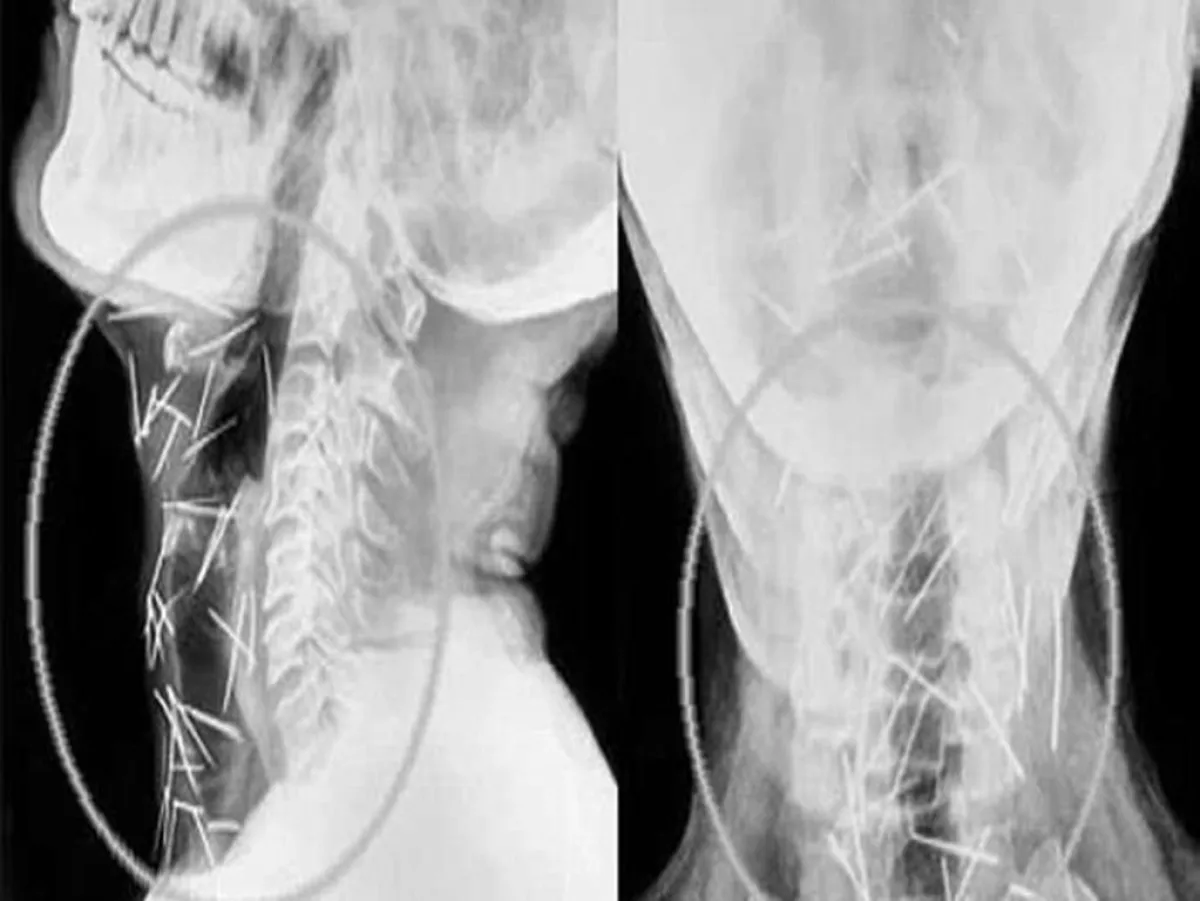

ووفقاً لـ«24»، في نهاية المطاف، قبل المعهد الآسيوي للعلوم الطبية التعامل مع الحالة، وخضع مينا لثلاث عمليات جراحية، لإزالة أكثر من 91 دبوساً من ذراعيه وقدميه وعنقه، البعض منها كان صدئاً للغاية، بعد أن تركت داخل جسده منذ عدة أشهر.

ويصر مينا، على أنه لم يغرس أياً من هذه الدبابيس داخل جسده، ولا يعرف كيف وصلت إليه، في حين يقول الدكتور لاليت موهان بارشار، إن عدم إصابة مينا بأية أضرار دائمة أشبه بالمعجزة.

وأضاف الدكتور بارشار الذي أجرى العمليات الجراحية للمريض، شكل إخراج الدبابيس من جسمه بأمان تحدياً كبيراً بالنسبة لنا، خاصة وأن بعضها كان مغروساً في الرغامى والمريء، وحتى في الشريان السباتي الذي يحمل الأوكسجين إلى الدماغ.